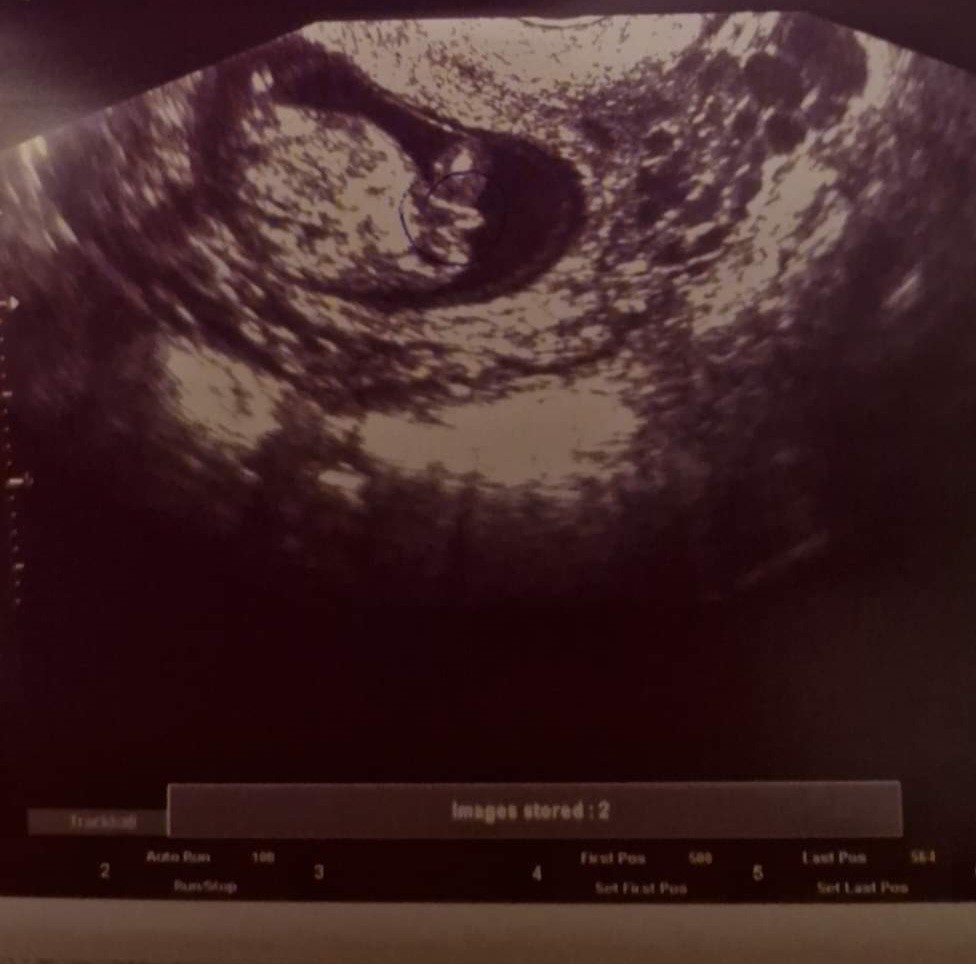

Hejka. To 12 tydzień ciąży. Chłopiec czy dziewczynka? Bo już sama nie wiem 🙈

To zaznaczyla mi Pani doktor która stwierdzila ze to chlopiec bo nie możliwe ze kośc ogonowa jest taka długa... w co nie bardzo wierzę bo to 12 tydzień i dziwne zeby byla tak na 100% pewna zwłaszcza ze ona jest juz troche starsza

Nadal nie wiadomo. W tym okresie może być chłopak, a zaraz dziewczyna. Także bym się uzbroiła w cierpliwość i zapytałam się lekarza w 17-18tc. Ja się w 17 dowiedziałam o płci. :)